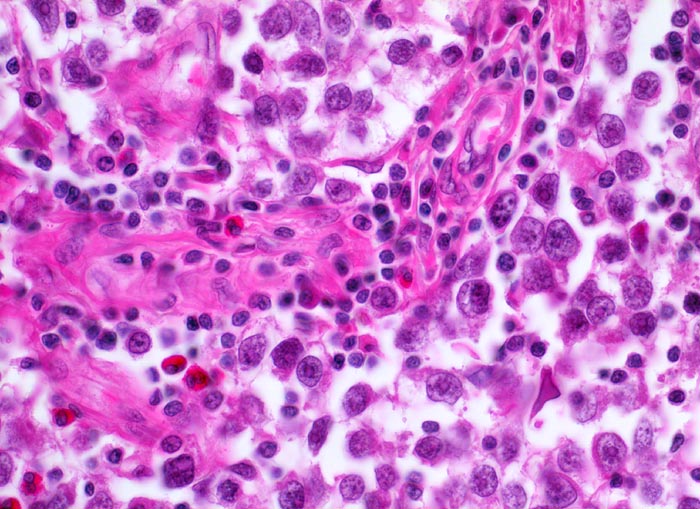

Makroskopisch imponieren Seminome als gut begrenzte weiche crèmefarbene Knoten oder diffuses Intiltrat. Mikroskopisch findet sich eine uniforme Population grosser Zellen mit prominentem zentralem Nukleolus, welche durch schmale Bindegewebssepten voneinander getrennte Nester bilden. Ein leukozytäres Entzündungsinfiltrat, synzytiotrophoblastäre Riesenzellen und Mikroverkalkungen können zusätzlich vorhanden sein. Gelegentlich induziert der Tumor eine ausgeprägte granulomatöse Entzündung. Dies kann zur Fehldiganose einer granulomatösen Orchitis führen.

• Scharf begrenzter Tumorknoten mit eosinophilen Nekrosearealen.

• Unterschiedlich breite solide Tumorzellstränge aus monomorphen Zellen mit grossen hyperchromatischen Kernen und einem solitären zentralen prominenten Nukleolus. Reichlich helles Zytoplasma mit scharfen Zellgrenzen.

• Schmale bindegewebige Septen mit Kapillaren und lymphoplasmazellulärem Entzündungsinfiltrat.